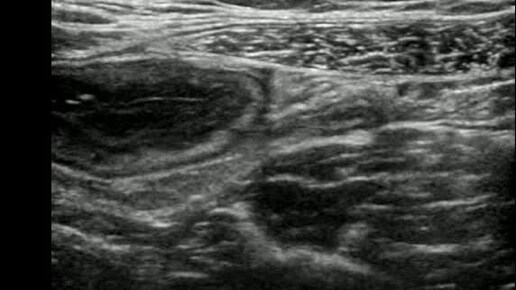

Видео к статье "Случай диагностики острого тифлита"Ссылка: https://dzen.ru/a/ZzGs8tEpkiCD8TE0

Ультразвуковые находки от врача УЗД Зорина Я.П.